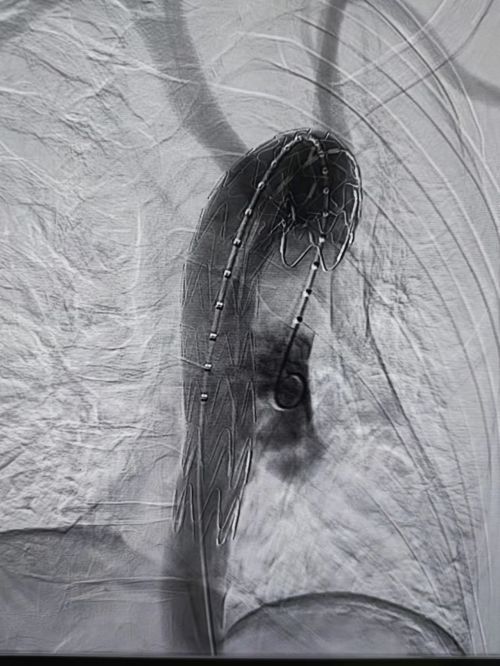

术前cta提示:异物刺破食道,纵膈感染积气及主动脉假性动脉瘤。

术前可以清楚地看到主动脉假性动脉瘤显影。

介入血管外科王庆主任、张昊医师等为患者施行主动脉假性动脉瘤腔内修复术。

术后,假性动脉瘤消失。

完善术前相关检查及准备后,王庆、姚袁晖、张昊等于2月24日晚21时许,在局麻下为患者施行主动脉假性动脉瘤腔内修复术。手术历时约15分钟,术后复查造影显示:主动脉支架位置良好,假性动脉瘤显影完全消失,未出现支架内漏或外渗,头颈部及其他重要血管血供未受影响。